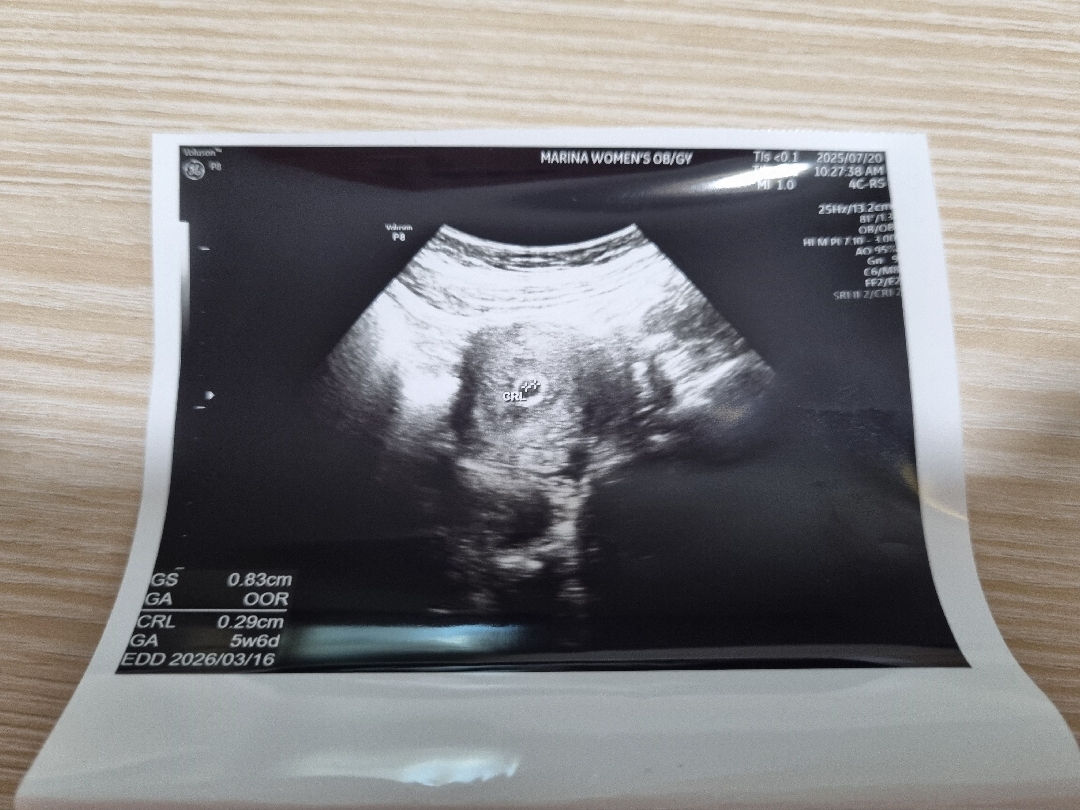

아기집 크기 변화

지난주 화요일에 첫 초음파 보고 오늘 새벽에 갑자기 소변에 피가 보여서 병원 간김에 초음파 봤어요~ 화요일은 0.74cm였고, 오늘은 0.83cm에요. 아기집 주변으로 피고임이 있어서 주수에 비해 아기집이 작다고 하시더라구요? 5일 지났으면 0.83cm보다 더 커야하는거 맞나요?ㅜㅜ 피고임 얼른 없어졌음 좋겠어요~